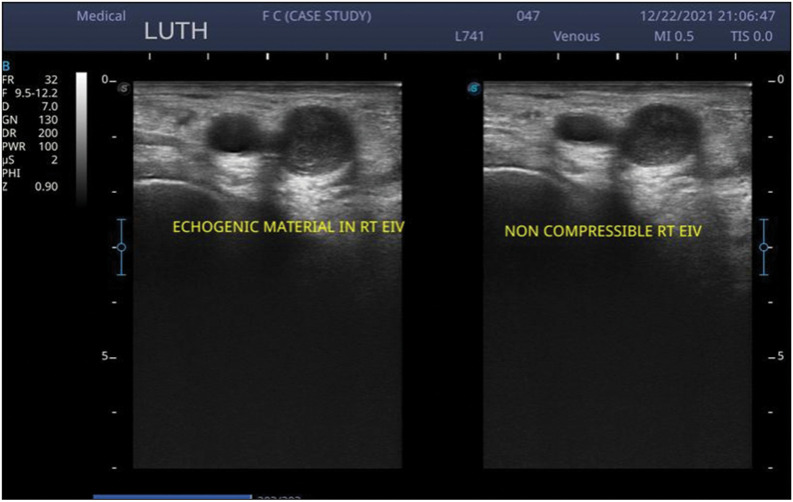

深静脉血栓形成(DVT)是世界范围内的突发公共卫生事件,也是造成全球疾病负担的主要因素。这是一个重要的原因发病率和死亡率在卧床病人,特别是那些与下肢骨折。早期发现深静脉血栓对患者的生存至关重要。本研究旨在评估住院骨科患者下肢深静脉血栓形成(LEDVT)的三重声像图特征,并确定与其发展相关的危险因素。这是一项描述性横断面研究,共有80名参与者:40名患有骨盆和下肢骨折(PELEF)的住院成人骨科患者和40名没有PELEF(非PELEF)的住院成人骨科创伤患者。在纳入研究前,获得机构伦理委员会的伦理批准,并得到所有参与者的同意。采用风险评估问卷对发生深静脉血栓的危险因素进行评估。对受试者进行威尔斯评分、d -二聚体测定和双下肢静脉三倍多普勒超声扫描。多普勒超声扫描发现7名(8.8%)参与者深静脉血栓形成。d -二聚体试验21例(52.5%)阳性,19例(47.5%)阴性。超声DVT结果与LEDVT患者的Wells评分相关。发生DVT的最高危险因素是近期卧床不起(92.5%)和重大创伤(87.5%),70.0%的LEDVT参与者和67.5%的非LEDVT参与者观察到这两个因素。与非PELEF对照组相比,PELEF组的LEDVT发生率更高。在本研究中,重大创伤、近期固定和侧浅静脉是深静脉血栓形成的主要危险因素。

Deep venous thrombosis (DVT) is a public health emergency worldwide and a major contributor to the global disease burden. It is a significant cause of morbidity and mortality amongst bedridden patients, especially those with lower extremity fractures. Early detection of DVT is crucial for the survival of the patient. This study aimed to assess the triplex sonographic features of lower extremity deep venous thrombosis (LEDVT) and identify risk factor(s) that are associated with its development in hospitalized orthopaedic patients. This was a descriptive cross-sectional study of a total of 80 participants: 40 hospitalized adult orthopaedic patients with pelvic and lower extremity fractures (PELEF) and 40 hospitalized adult orthopaedic trauma patients without PELEF (non-PELEF). Ethical approval was obtained from the institutional ethics committee and consented to by all the participants before inclusion. The risk factors for DVT were assessed using a risk assessment questionnaire. Wells score, D-dimer assay, and triplex Doppler ultrasound scanning of both lower limb veins were performed on the participants. Doppler ultrasound scan detected DVT in seven (8.8%) participants. D-dimer test was both positive in 21 (52.5%) and negative in 19 (47.5%) participants. Sonographic DVT findings correlated with Wells scores in those with LEDVT amongst cases. The highest occurring risk factors for DVT were being recently bedridden (92.5%) and major trauma (87.5%) which were observed in 70.0% of participants with LEDVT and 67.5% without LEDVT. LEDVT occurred more in the PELEF case group compared to the non-PELEF controls. Major trauma, recent immobilization, and collateral superficial veins were the major risk factors for DVT in this study.